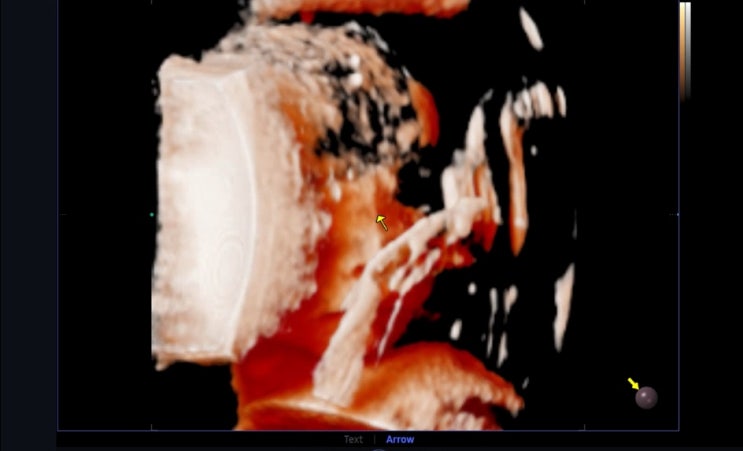

지금까지 별다른 이벤트 없이 우리또리는 무럭무럭 잘크고 있었다 주수보다 작다, 피가 비친다던지 그런일...